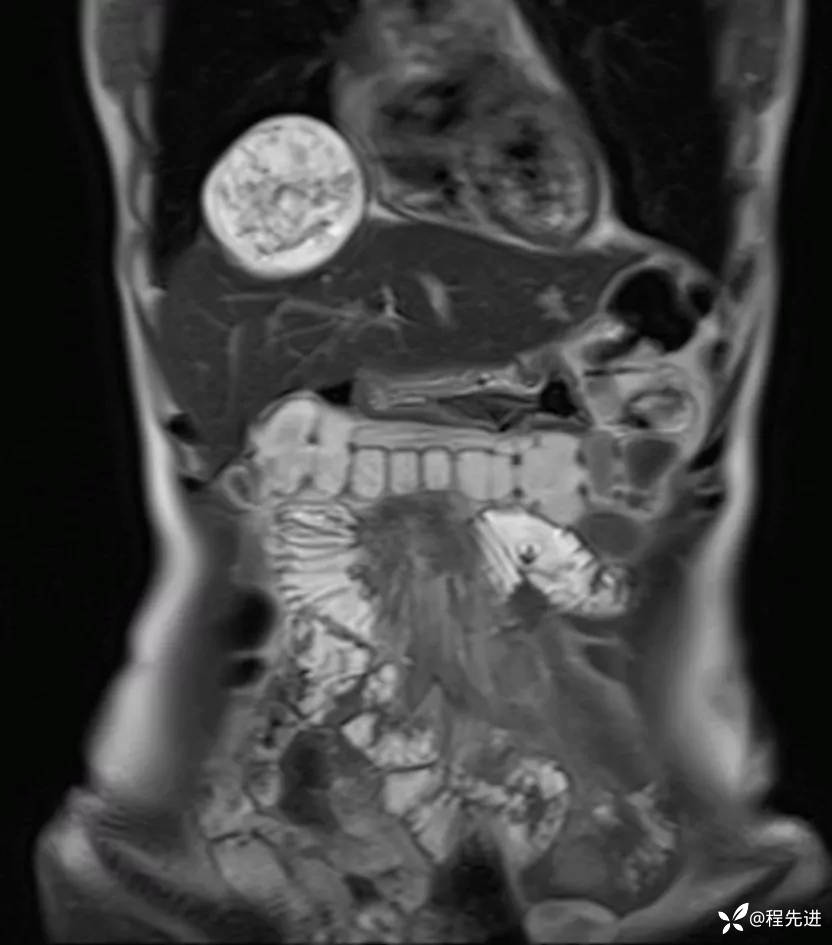

MRI平扫+增强:

img